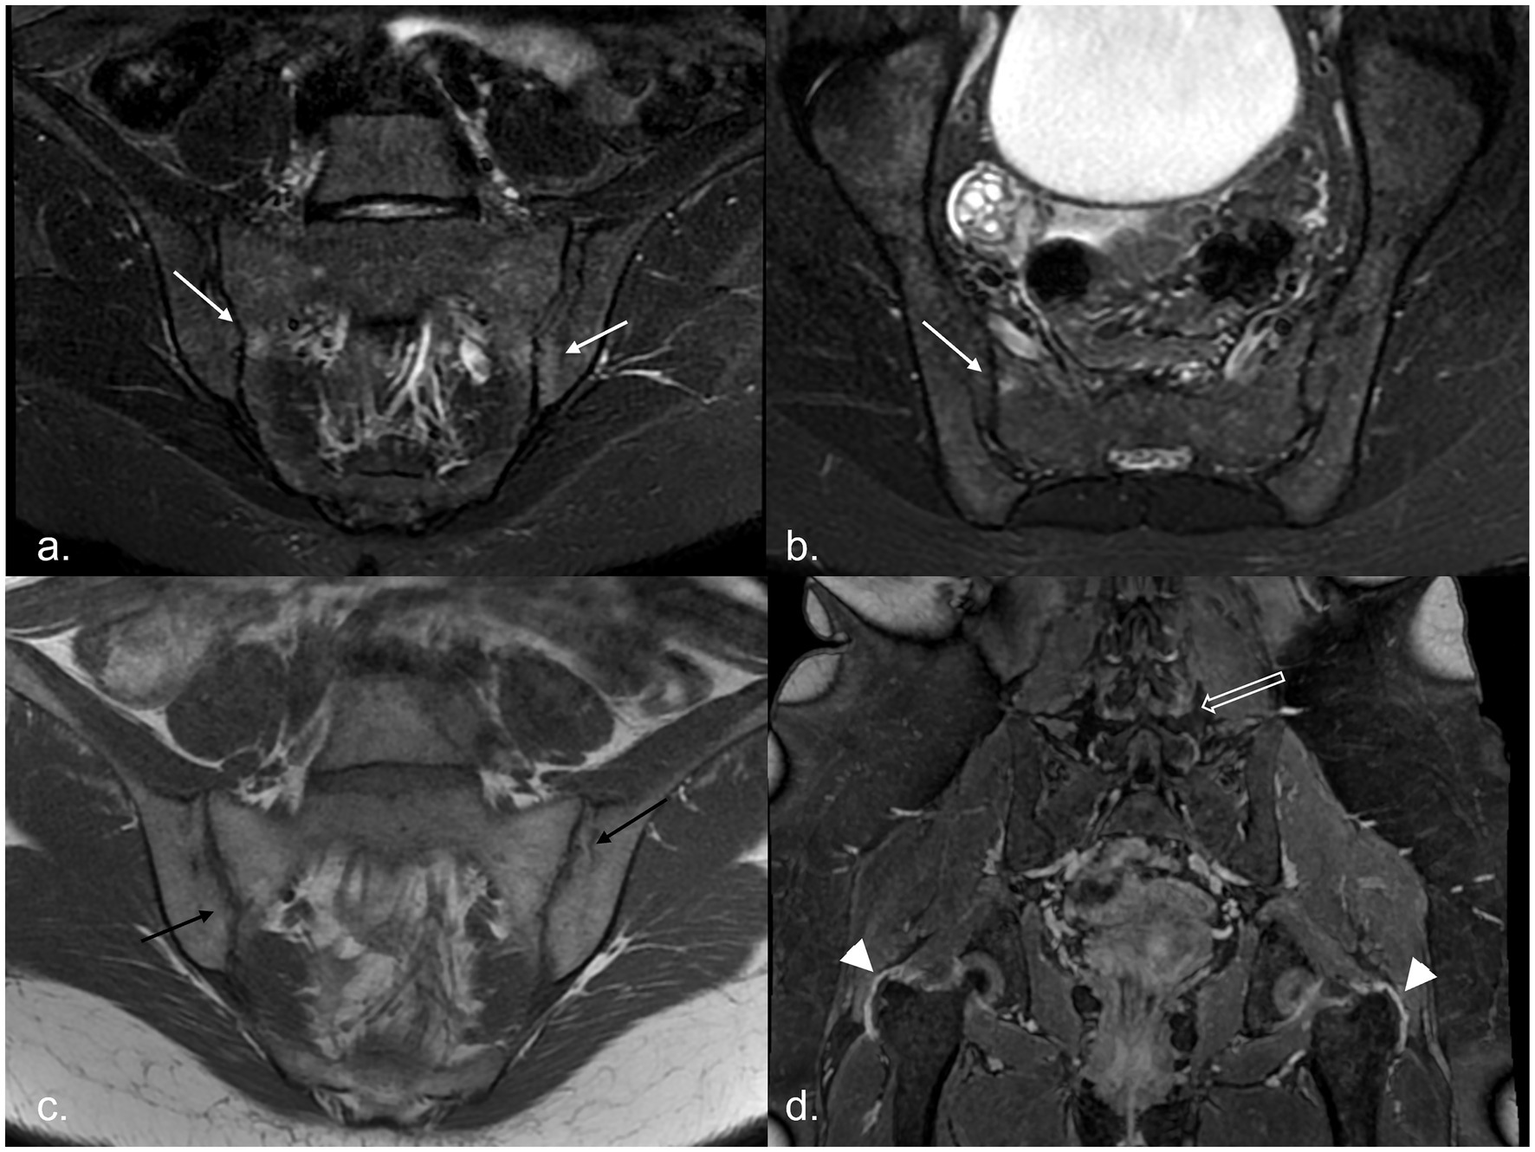

Figure 1

MR examination of a 20-year-old woman with recurrent fever: it shows areas of subchondral BME on the right sacral and left iliac sides of the sacroiliac joints [white arrows, panel (a) in the oblique coronal plane and panel (b) in the oblique axial plane], associated with multiple bilateral joint erosions [black arrows in panel (c)]. After administration of CM, in the 3D panoramic sequence for the hip, trochanteric enthesitis (arrowhead) and facet capsulitis (empty white arrow) are evident [panel (d)]. BME, bone marrow edema; CM, contrast media.